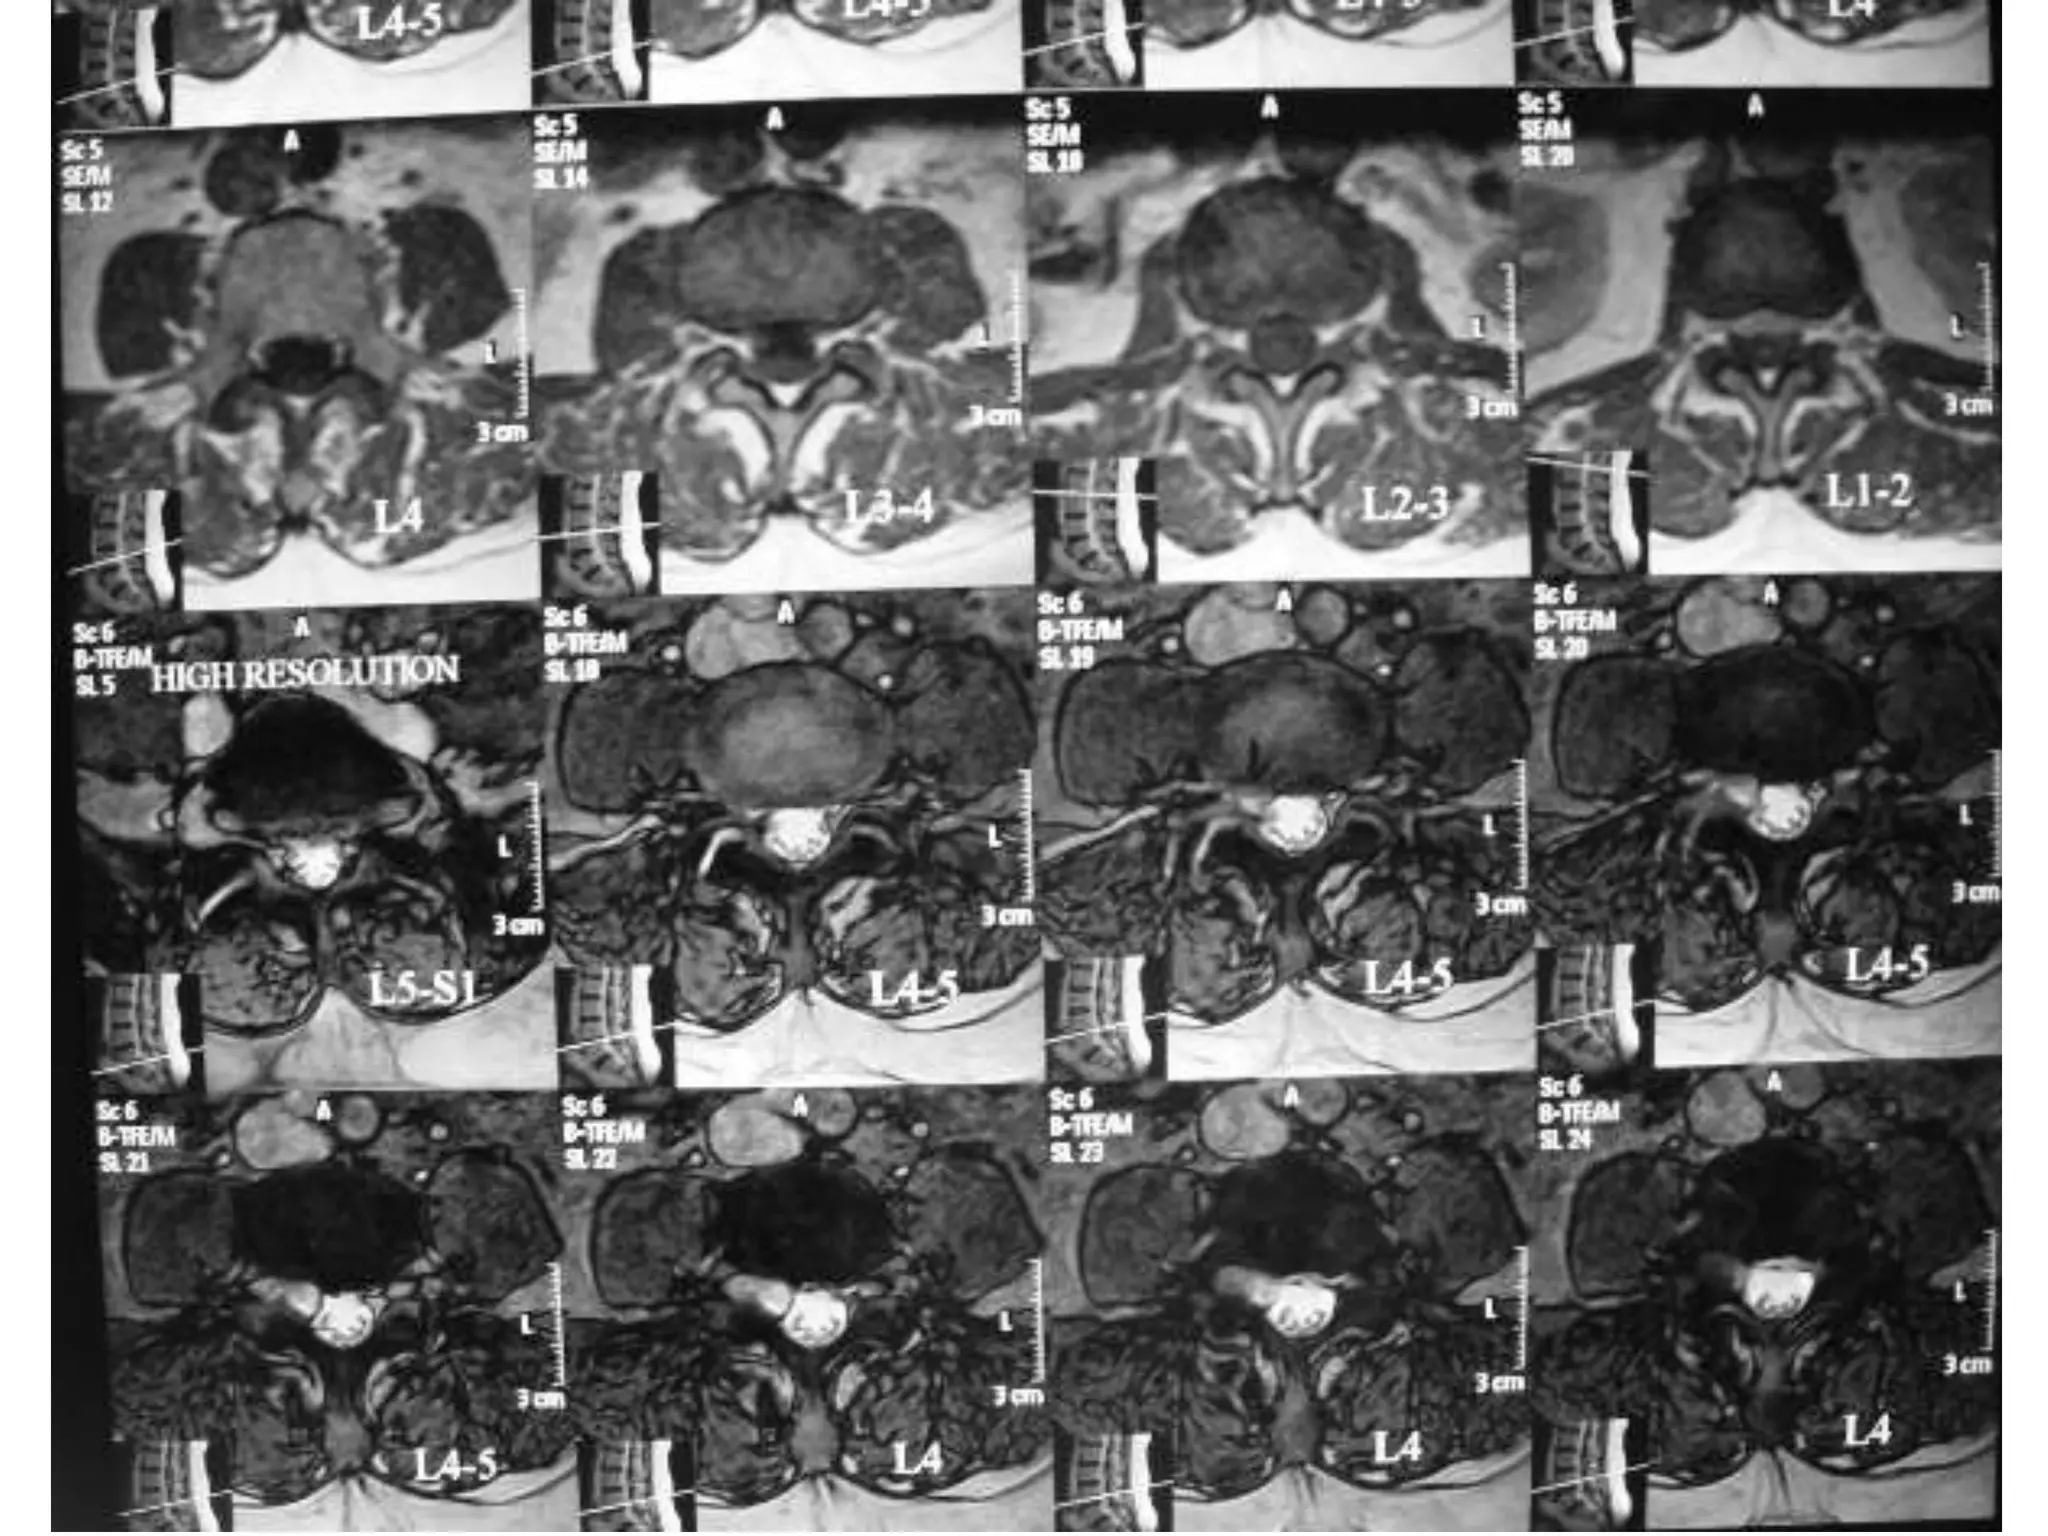

Dynamic Degenerative InstabilityFlexionExtension

Spondylolisthesis Gr. III

Cervical Degenerative Listhesis